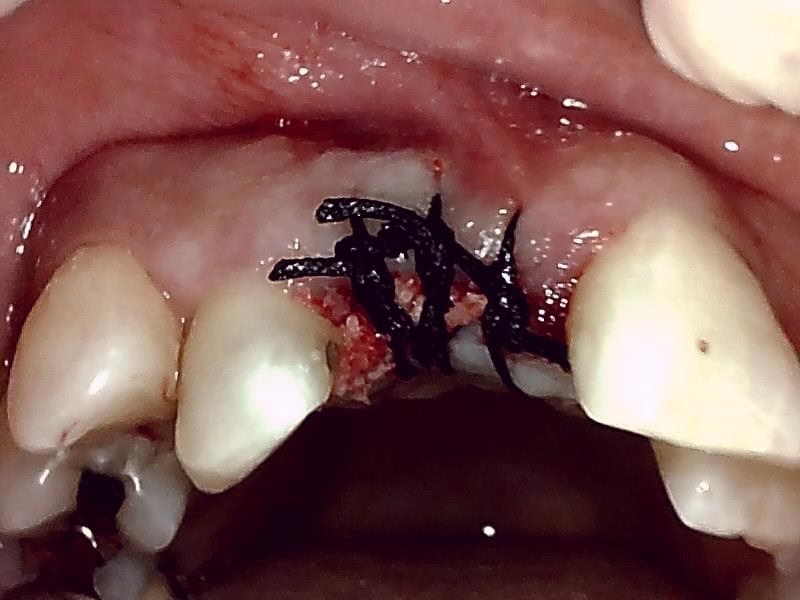

減張切開した歯肉を縫合した状態です。

ヒーリングアバットメント装着して歯肉を縫合する。